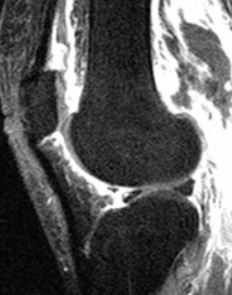

МРТ коленного сустава. Т2-взвешенная сагиттальная МРТ. Септический артрит.